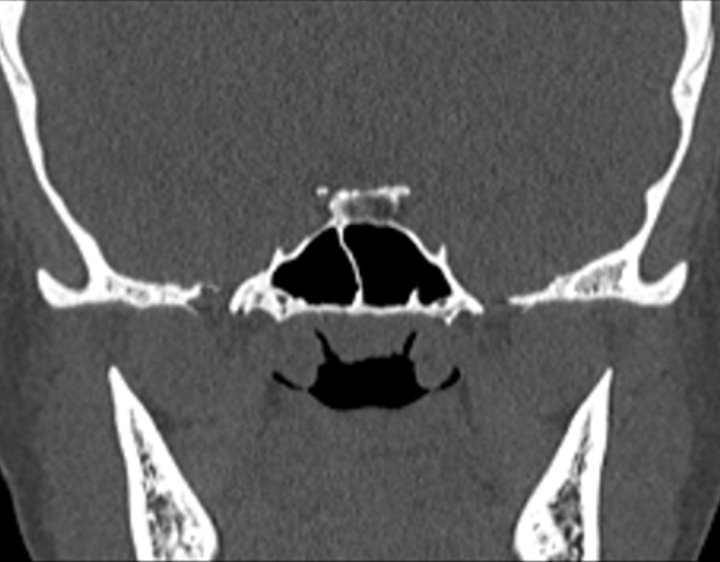

Click any image for labels.